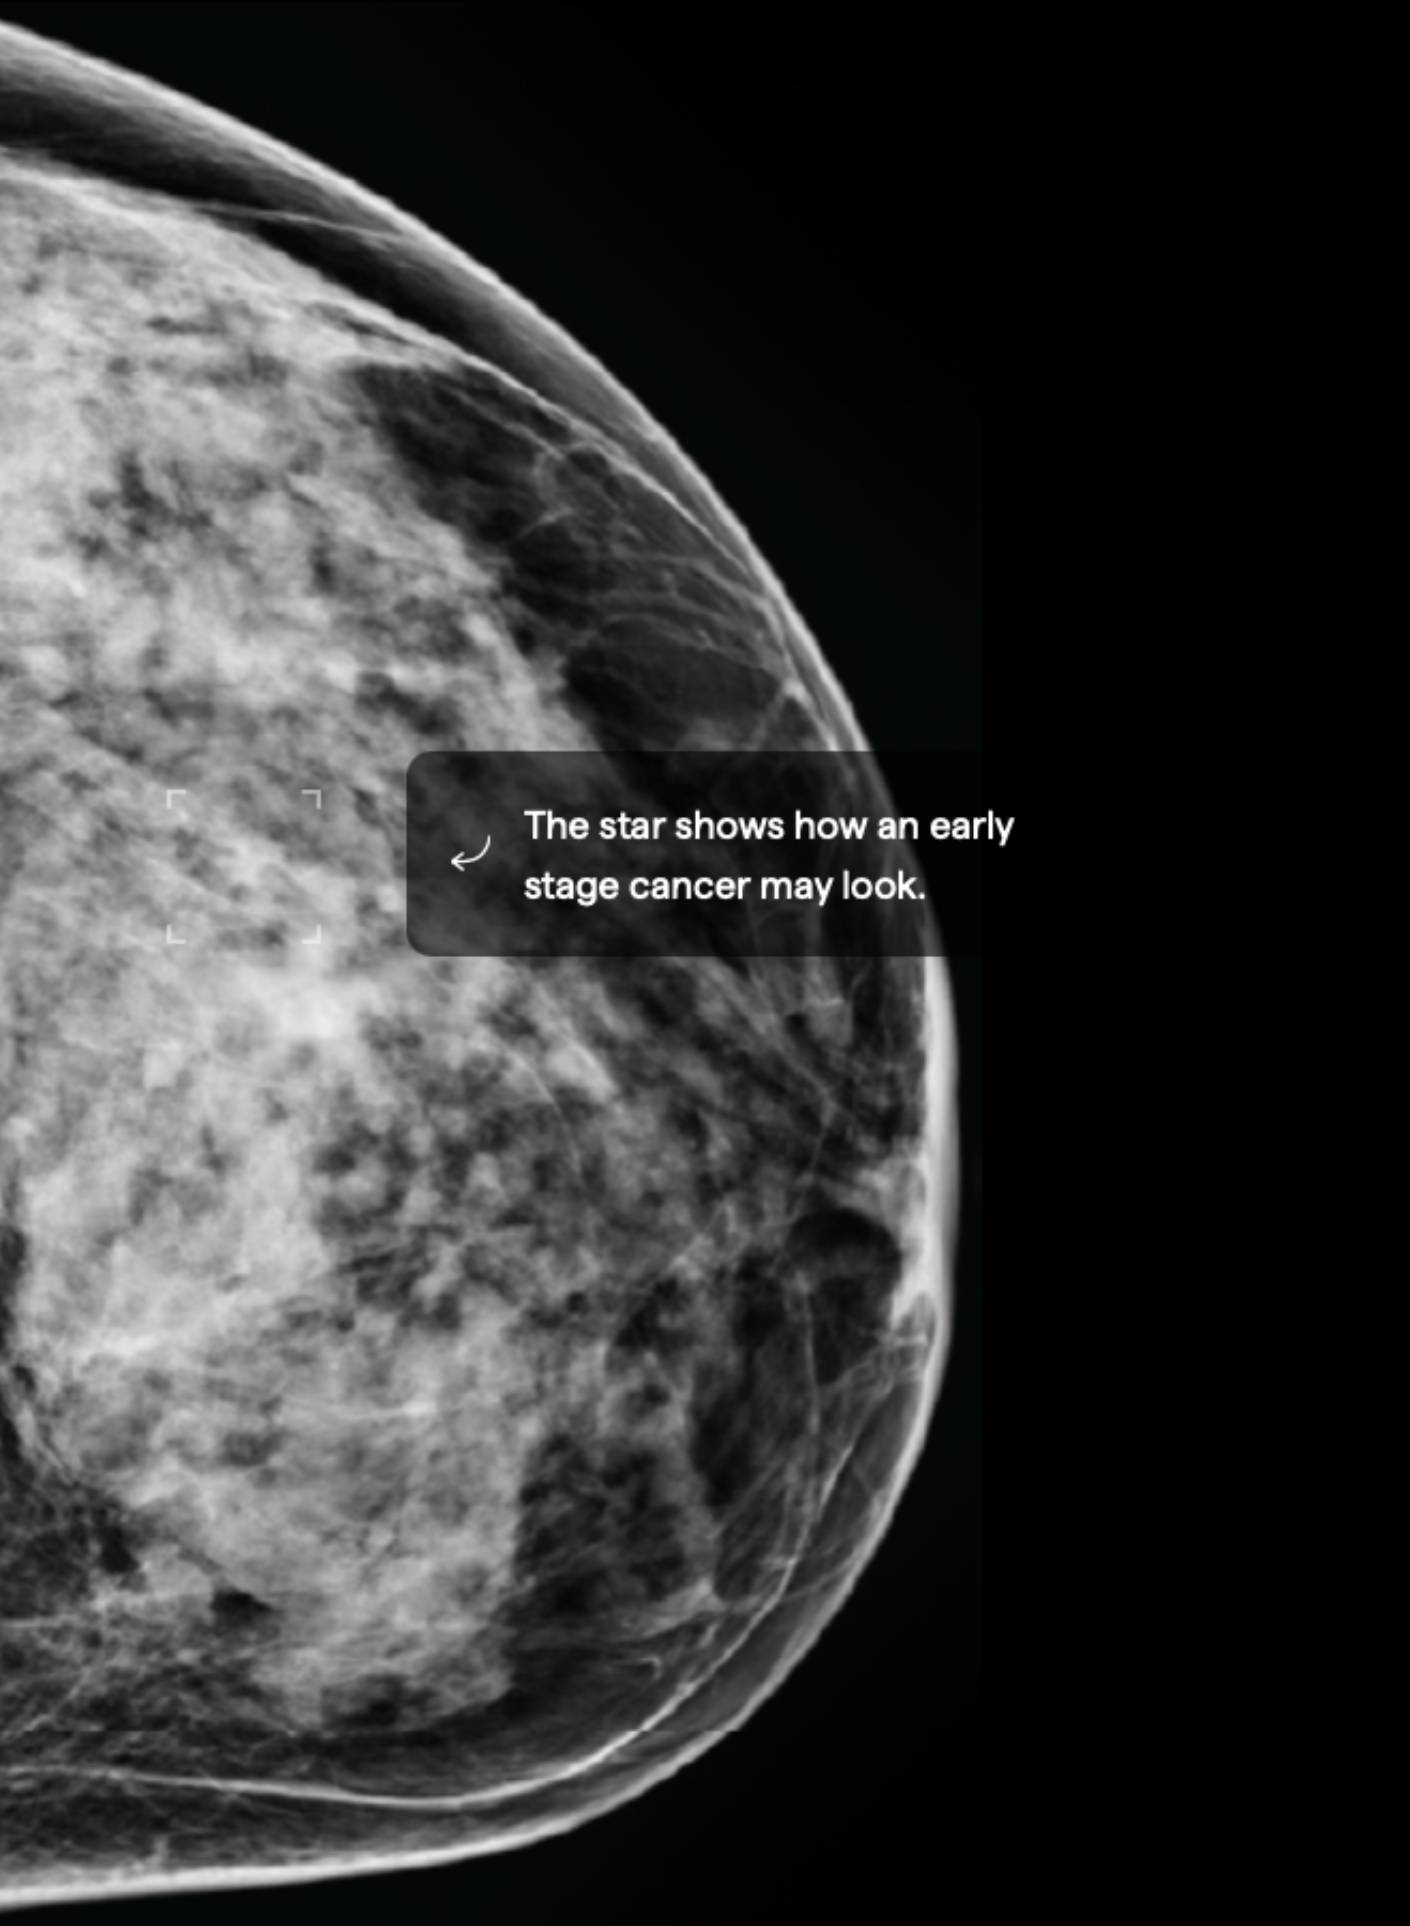

About 40% of female breasts fit category “C”. They are referred to as “heterogeneously dense breasts”.1

Your dense tissue could hide masses on your mammogram.3 Consider asking your doctor if additional ultrasound or MRI imaging should become part of your screening schedule. Also consider asking about a risk assessment to help both of you better understand your lifetime risk for breast cancer.

15.5% Mammographic Density

About 10% of female breasts fit category “D”. They are referred to as “extremely dense breasts”.1

Women with high breast density may have a greater risk of developing breast cancer. High breast density also makes it harder to detect breast cancer.3 Consider asking your doctor about adding ultrasound and/or MRI imaging to your screening schedule. Also consider asking about a risk assessment to help both of you better understand your lifetime risk for breast cancer.